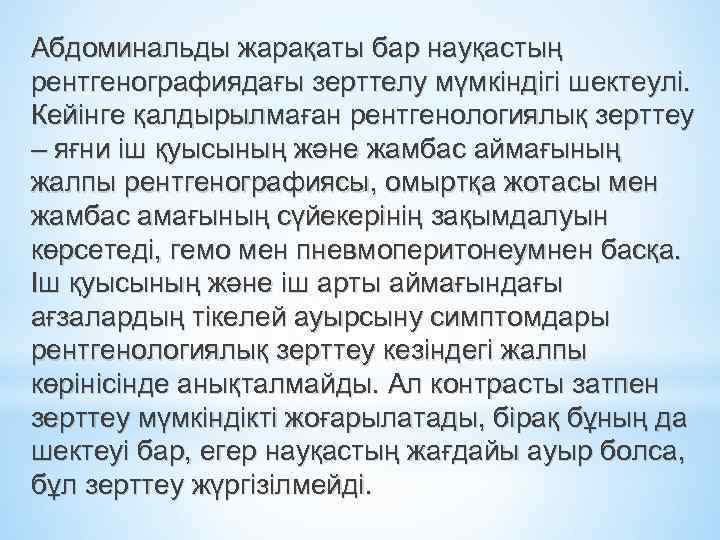

Абдоминальды жарақаты бар науқастың рентгенографиядағы зерттелу мүмкіндігі шектеулі. Кейінге қалдырылмаған рентгенологиялық зерттеу – яғни іш қуысының және жамбас аймағының жалпы рентгенографиясы, омыртқа жотасы мен жамбас амағының сүйекерінің зақымдалуын көрсетеді, гемо мен пневмоперитонеумнен басқа. Іш қуысының және іш арты аймағындағы ағзалардың тікелей ауырсыну симптомдары рентгенологиялық зерттеу кезіндегі жалпы көрінісінде анықталмайды. Ал контрасты затпен зерттеу мүмкіндікті жоғарылатады, бірақ бұның да шектеуі бар, егер науқастың жағдайы ауыр болса, бұл зерттеу жүргізілмейді.